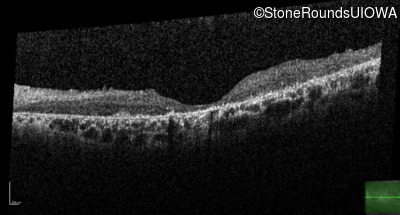

Optical Coherence Tomography - Right - 20/400 sc

Exemplar / OCT Stack